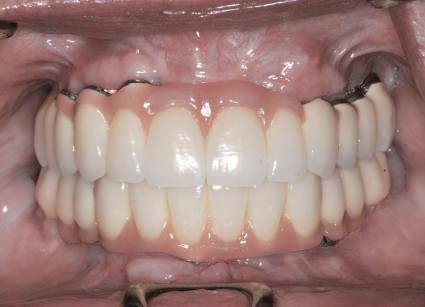

Dacă însă implanturile sunt plasate prea vestibular sau prea superficial, componentele nu permit un design adecvat al bontului, pentru că plasarea marginii este limitată iar conturul facial şi proximal poate fi compromis (fig. 1, 2).

Figurile 3, 4. Întrucât poziţia implantului era mezială faţă de ideal, bonturile individualizate s-au conceput plate pe profilul mezial, dar au prezentat provocări în privinţa conturării restauratoare. 5. Restaurările implantare de la nivelul 1.2. şi 2.2. susţin o FPD metalo-ceramică cimentată între incisivii laterali.

Figurile 1, 2. Compromisurile conturului vestibular şi proximal sunt evidente. Implantul este la nivel tisular, tehnicianul neputând gestiona plasarea marginii sau a profilului intrasulcular pentru a îmbunătăţi estetica. Dacă se concepea un design tradiţional cu hexagon extern, marginea restauratoare s-ar fi putut plasa foarte aproape de interfaţa bont-implant, cu gestionarea mai bună a spaţiului.